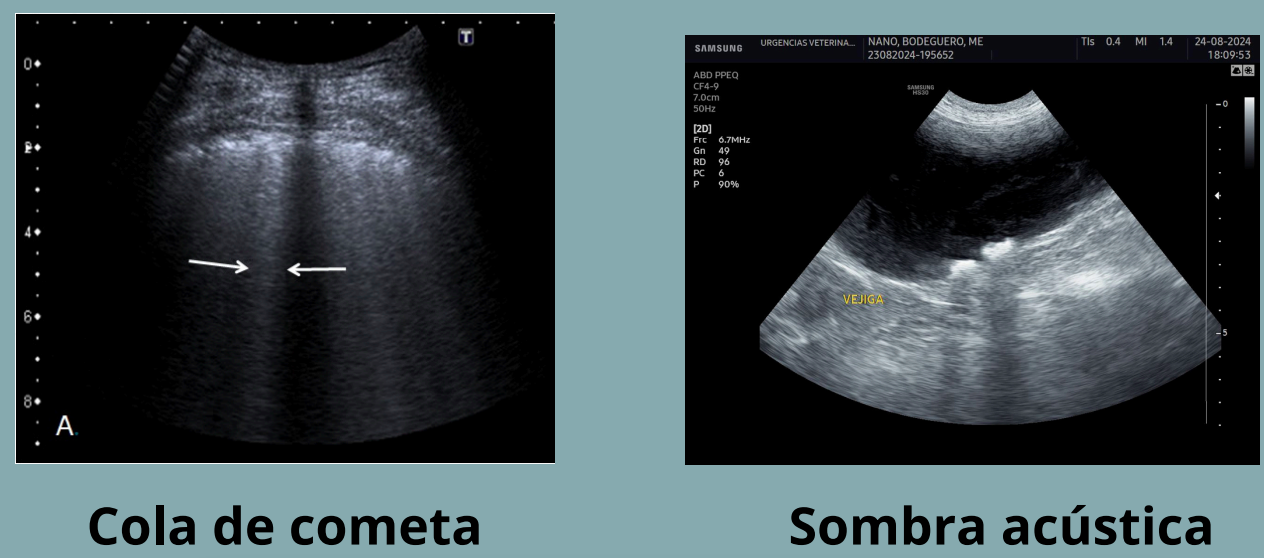

Artefactos: Cola de cometa:

- Como el de reverberación, tambien se quedan atrapadas las ondas en gas pero en vez de ser una masa son pequeñas burbujas. Se ve como multiples refracciones proximas entre si

- El resultado son lineas hiperecogenica corta y brillante que se estrecha en profundidad

- Ejemplo: aire en pulmon, pequeños cuerpos metalicos

NO CONFUNDIR COLA DE COMETA Y SOMBRA ACUSTICA. La cola de cometa presenta haces hiperecoicos, la sombra acustica haces hipoecoicos.

Sombra acústica

- Las ondas de sonido no pueden atravesar una estructura densa (material mineral) o un estrato de gas.

- La imagen generada presenta una línea superficial hiperecogénica que describe la superficie de la estructura, a partir de la cual, pierdo completamente la visualización de los estratos profundos (región oscura).